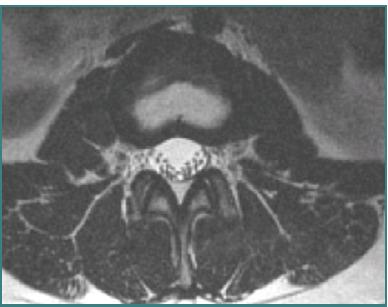

Vascular injuries during anterior lumbar interbody fusion (ALIF) are reported in the existing literature with an incidence rate ranging from 1% to 24%, predominantly venous lacerations owing to branch vessel avulsions during mobilization and retraction. Arterial injuries, although less frequent, occur at an incidence of 0.45% to 1.5% and are mainly characterized by thromboses; aortic lacerations remain exceptionally rare. L4-L5 and L5-S1 are the two levels associated with the majority of vascular complications. Preoperative 3D CT angiography is paramount and a gold standard, as it illustrates the anatomic variations of the iliolumbar vein, the aorta, and the vena cava bifurcation, providing the surgeon with valuable information regarding operative trajectories. Regarding preventive measures, venous laceration, the most common vascular injury, occurs less frequently when employing nonthreaded interbody grafts such as iliac crest autograft or femoral ring allograft. Also, left iliac artery thrombosis can be decreased intraoperatively by intermittent release of retraction. Managing vascular complications includes compression for bleeding control, Trendeleburg positioning of the patient and venorrhaphy, and the employment of topical clot-forming enhancement and/or hemostatic agents. Although postoperative lower limb duplex ultrasonography can be an effective tool, magnetic resonance venography (MRV) and intravenous catheterization (IVC) remain the gold standards for diagnosing postoperative pelvic vein thrombosis in cases of iliac vein repair after anterior spine surgery. This paper aimed to highlight the incidence of major vascular injury during ALIF surgery, describe predisposing risk factors, and discuss management techniques while highlighting the requirement for more sensitive and factor-specific studies to attain a more profound understanding of the mechanism of vasculature complications during ALIF procedures.

现有文献报道了腰椎前路椎间融合术(ALIF)期间血管损伤的发生率在1%至24%之间,主要是由于在松动和牵开过程中分支血管撕脱导致的静脉撕裂。动脉损伤虽然较少见,发生率为0.45%至1.5%,主要表现为血栓形成;主动脉撕裂极为罕见。L4-L5和L5-S1是与大多数血管并发症相关的两个节段。术前三维CT血管造影至关重要,是金标准,因为它能显示髂腰静脉、主动脉和腔静脉分叉的解剖变异,为外科医生提供有关手术路径的有价值信息。关于预防措施,使用非螺纹椎间融合器(如髂嵴自体骨移植或股骨环同种异体移植)时,最常见的血管损伤——静脉撕裂的发生率较低。此外,术中通过间歇性松开牵开可减少左髂动脉血栓形成。处理血管并发症包括压迫止血、患者头低脚高位和静脉缝合,以及使用局部促凝增强剂和/或止血剂。虽然术后下肢双功超声检查可能是一种有效的工具,但磁共振静脉造影(MRV)和静脉插管(IVC)仍然是诊断前路脊柱手术后髂静脉修复病例中术后盆腔静脉血栓形成的金标准。本文旨在强调ALIF手术期间主要血管损伤的发生率,描述易感危险因素,并讨论处理技术,同时强调需要进行更敏感和针对特定因素的研究,以更深入地了解ALIF手术期间血管并发症的机制。